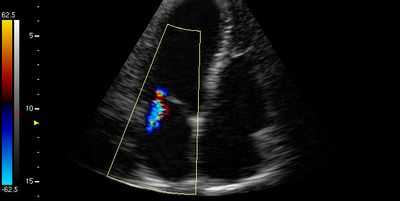

снижение выброса из ЛЖ - признак митральной недостаточности

Тем не менее, подтвердить стеноз митрального отверстия достоверно можно только с помощью визуализирующих методов исследования, в частности, с помощью эхокардиоскопии, или УЗИ сердца. Данный метод позволяет оценить площадь митрального кольца и степень утолщения (гипертрофии) предсердий, увидеть утолщенные, спаянные створки, измерить давление в сердечных камерах. Одним из главных показателей, оцениваемых при митральном стенозе, является фракция выброса (ФВ), показывающая кровяной объем, изгоняемый в аорту и далее по сосудам всего организма Нормальный показатель ФВ составляет не менее 55%, при митральном стенозе может существенно снижаться, достигая критических значений - 20-30% при тяжелом стенозе.

митральная регургитация на ЭхоКГ

Помимо УЗИ, косвенные признаки регургитации можно обнаружить на ЭКГ, при тщательной аускультации сердца и оценке симптоматики.